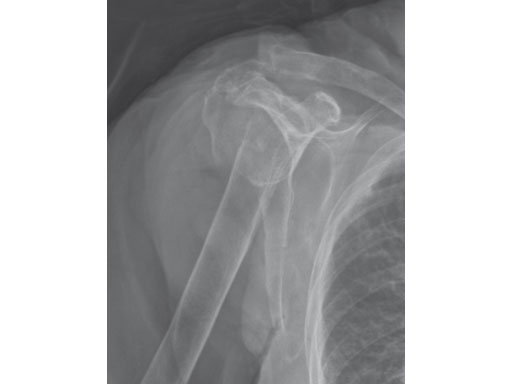

A 76-year-old woman suffered a low-energy fall at home.

Case provided by Stefaan Nijs, Leuven, Belgium